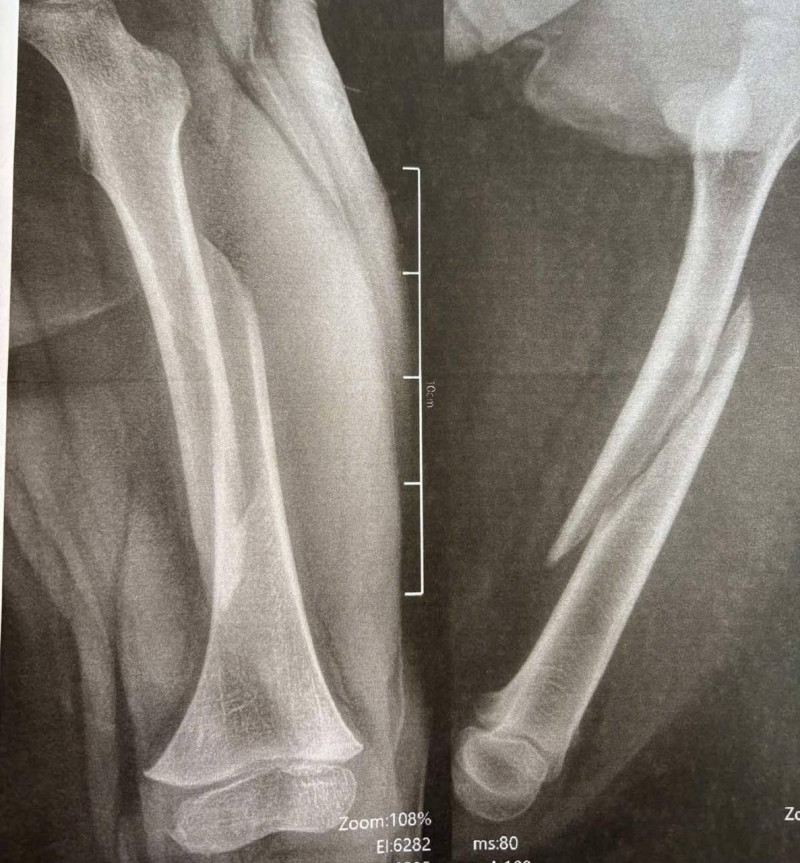

Наслідки падіння для 13-річного Максима — перелом стегнової кістки зі зміщенням і кісток гомілки.

«Переломи дуже серйозні,— говорить ортопед-травматолог дитячий Богдан Петерчук. — Попри це завдяки інтрамедулярному остеосинтезу через 2 дні після операції Максим вже рухає ногою та швидко реабілітується. Оперативне втручання ми зробили через невеликі розрізи на стегні та гомілці».